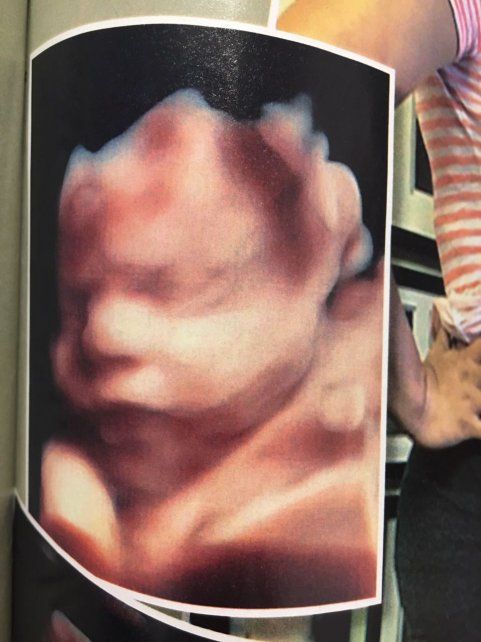

El exitoso empresario teatral mostró por primera vez en revista Gente las ecografías de su hijo y contó cómo fue el encuentro con la madre subrogada.

El artista, que espera a Dionisio para el 15 de abril, presentó a Giselle, la madre subrogada, y muestra por primera vez el rostro de su bebé en la última ecografía 4D.